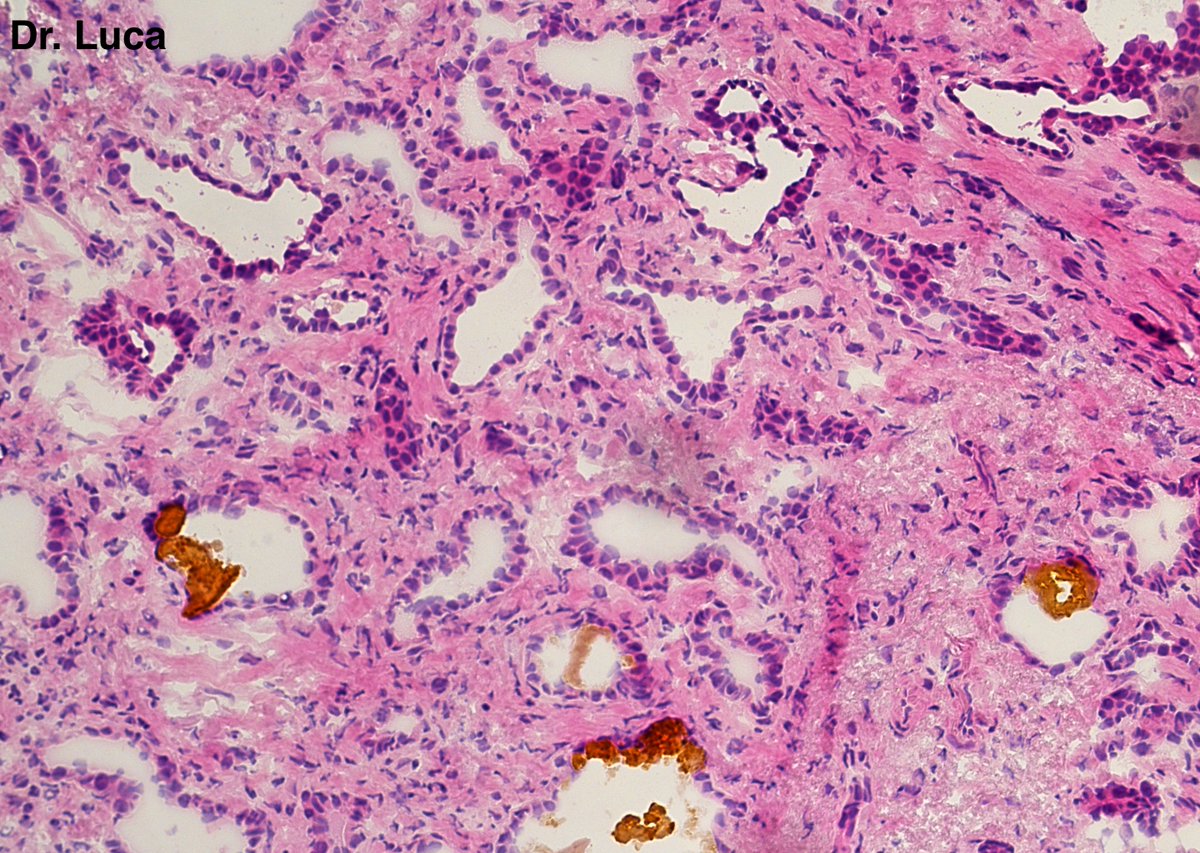

I've seen too many cases this week and in the end I got lost...what do we have here?@pepeheffernan @PoloniaAntonio @JMGardnerMD @kriyer68 @niyatis25 @bansar7 @goziemnweke @AkgulMd @slusagar @thejourneymate @Nachofrarub @VHNguyenMD @Pathmath1 @ivanaspath #Pathology #PathTwitter

8

9

28